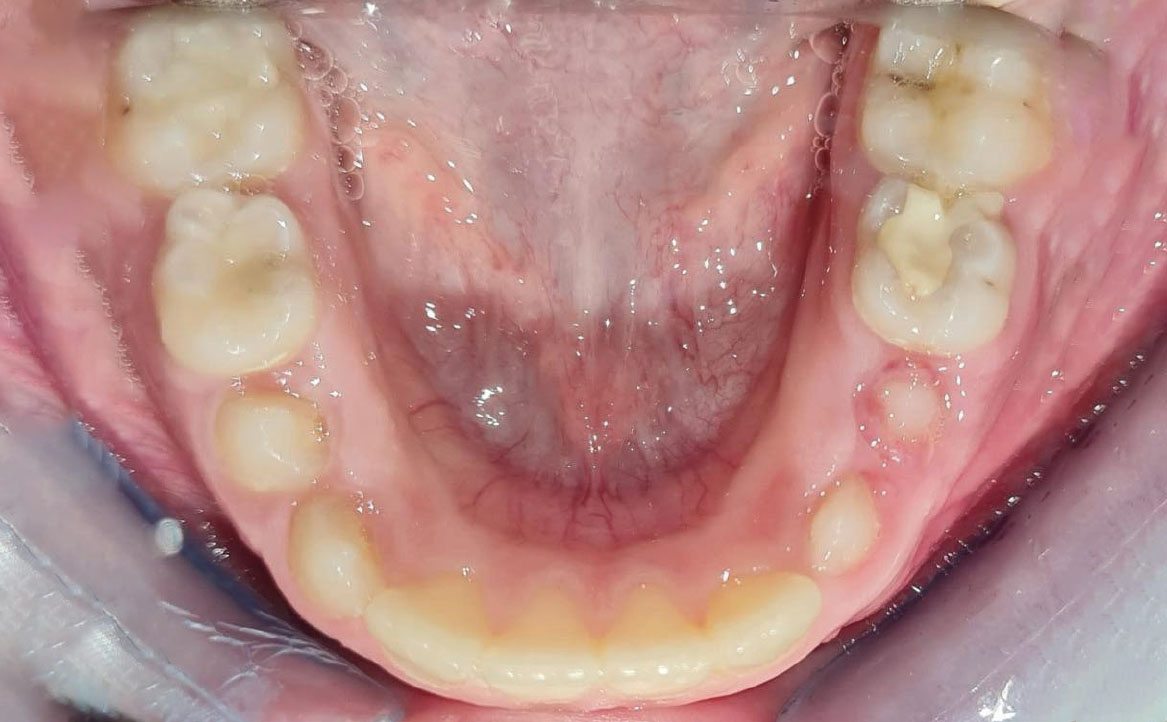

Fig. 7A Foto dell'arcata inferiore.

L’overjet e l’overbite sono entrambi ridotti in massima intercuspidazione. Trasversalmente il mascellare superiore è contratto (fig. 4-7).